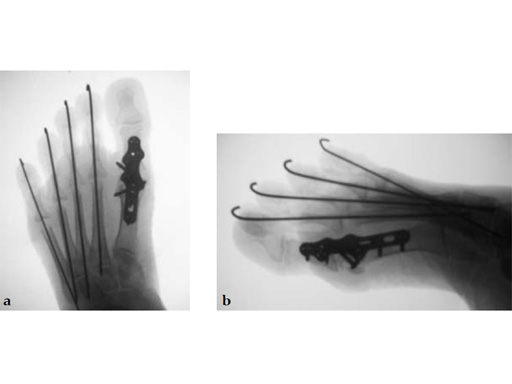

Case 3: First TMT fusion plate

A 48-year-old woman, with hallus valgus and hypermobile medial column, also resulting in pes plano abductovalgus (flatfoot).

Case provided by Andrew Sands, New York, New York, USA

Surgery consisted of first TMT and intertarsal corrective osteotomy plus fusion with movement of the first MT lateral and plantar. This corrects the hallus valgus as well as the PPAV (and stabilizes the medial column).

Case 4: First TMT fusion plate

A 60-year-old woman with pes plano abductovalgus (flatfoot deformity).

The patient was treated by headless compression screw 6.5 tuber osteotomy, TMT plantarflexing osteotomy, and first TMT fusion a plate.